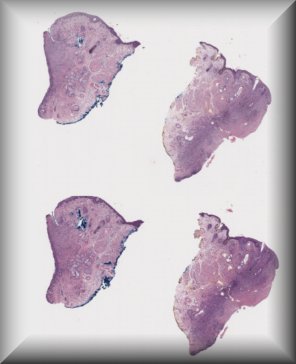

Patricia Chévez Barrios (Houston): 2 year-old-boy with history of group D unilateral retinoblastoma s/p systemic chemotherapy, cryotherapy and intravirteous chemotherapy. Enucleated for progressive disease. |

|